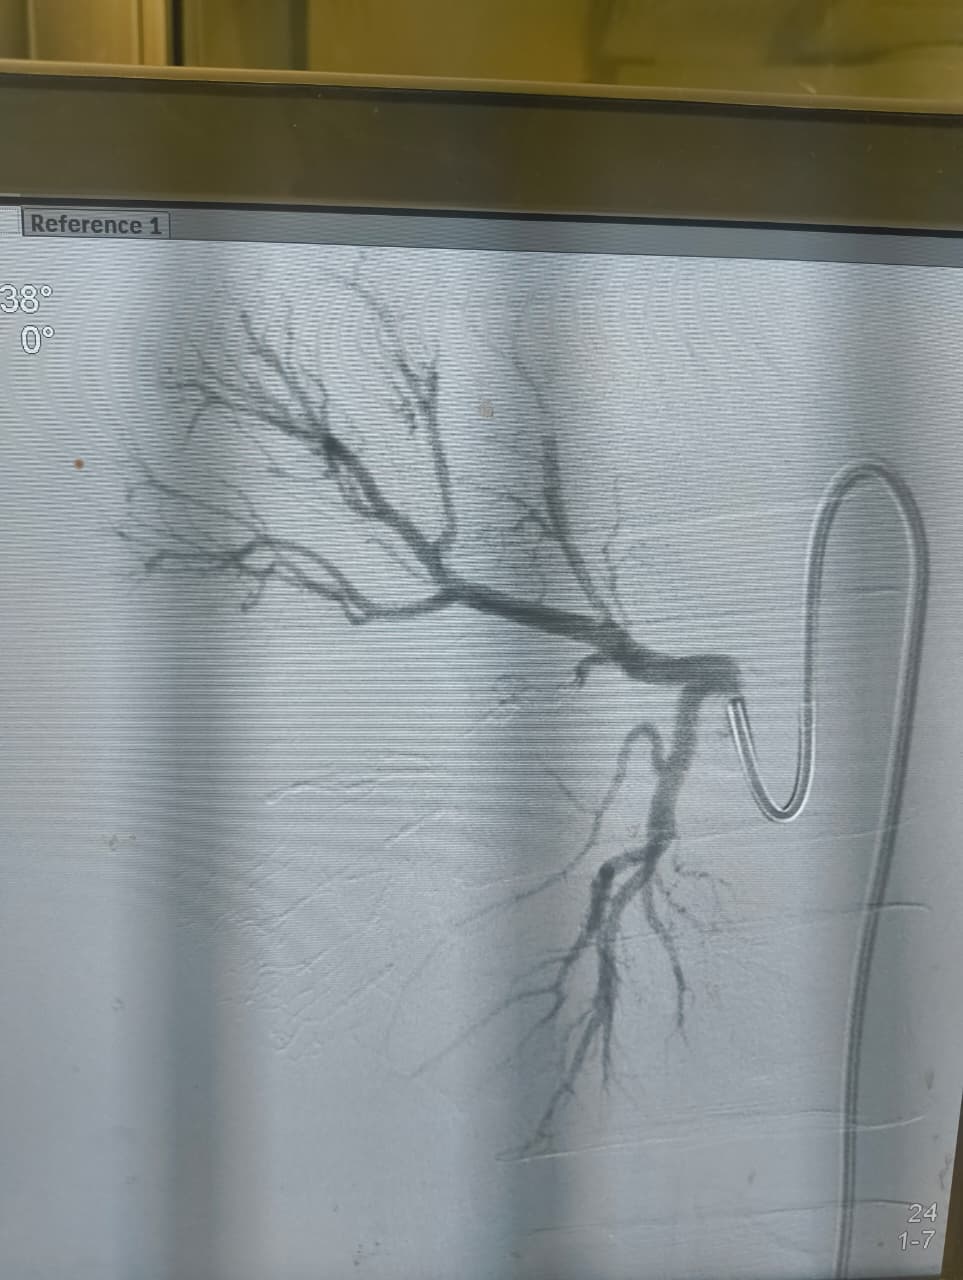

نجح الفريق الطبي بوحدة الأشعة التداخلية في إنقاذ شاب مصاب تعرّض لحادث أدى إلى قطع جزئي في الشريان الكلوي الأيمن مصحوبًا بتجمع دموي كبير خلف الغشاء البريتوني، وذلك دون اللجوء إلى استئصال الكُلى أو التدخل الجراحي التقليدي.

وتمكن فريق وحدة الأشعة التداخلية برئاسة الدكتور محمود غلاب، أستاذ الأشعة التداخلية بطب كفر الشيخ، من إجراء تدخل طارئ ناجح، تم خلاله سد التمدد الشرياني مع الحفاظ الكامل على التغذية الدموية لباقي أنسجة الكُلى، وهو ما يُعد من أبرز وأهم مميزات الأشعة التداخلية.

وقال الفريق الطبي، إن الأشعة التداخلية تتميز بقدرتها الفائقة على الوصول إلى أدق شرايين الجسم وإجراء تدخلات عالية الدقة والصعوبة دون أي تدخل جراحي، بل ودون الحاجة إلى التخدير الكلي.